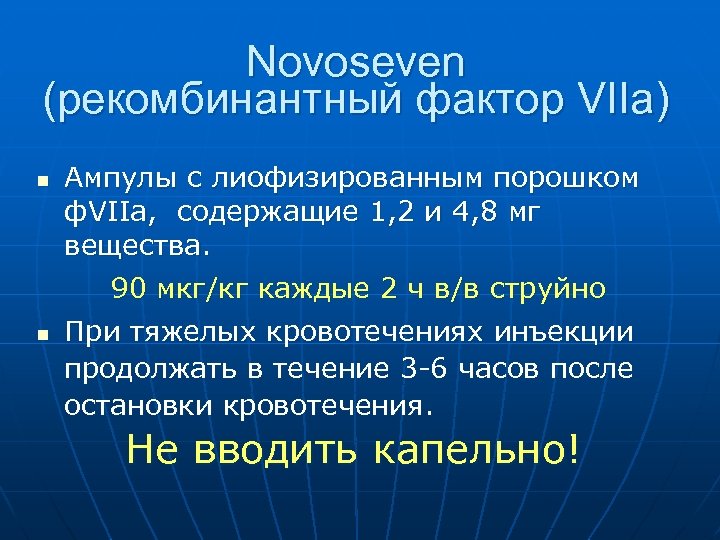

Novoseven (рекомбинантный фактор VIIа) n n Ампулы с лиофизированным порошком ф. VIIa, содержащие 1, 2 и 4, 8 мг вещества. 90 мкг/кг каждые 2 ч в/в струйно При тяжелых кровотечениях инъекции продолжать в течение 3 -6 часов после остановки кровотечения. Не вводить капельно!